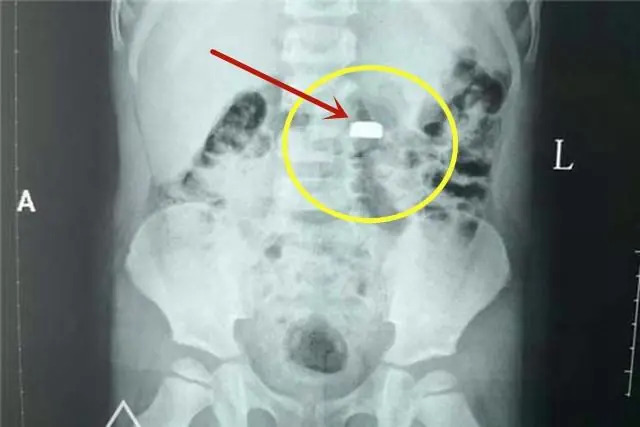

Viên pin cúc áo mà bé trai 3 tuổi của chị Linlin nuốt phải gây nguy hiểm dù tới bệnh viện ngay sau đó

Quan trọng nhất, cần nhớ, dù dùng mật ong hay phương pháp sơ cứu nào cũng phải đưa trẻ đi cấp cứu càng sớm càng tốt ngay sau đó. Thông báo rõ hoặc mang theo loại pin trẻ nuốt phải. Bác sĩ sẽ sắp xếp chụp X-quang, CT và ưu tiên phương pháp nội soi để gắp pin ra sớm nhất có thể, ngăn chặn hóa chất rò rỉ phá hủy nội tạng.